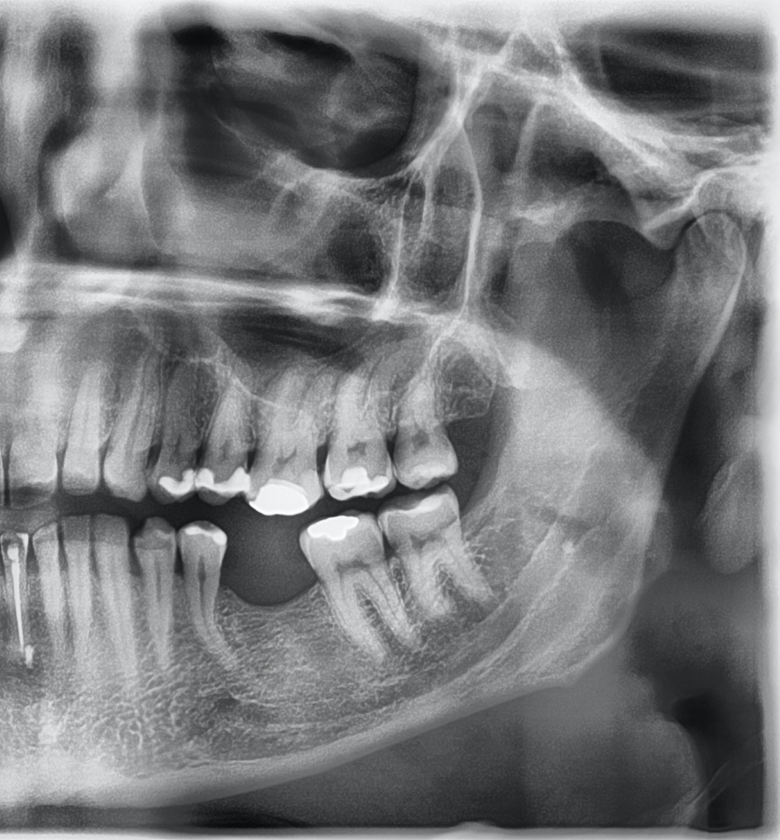

Do kliniki zgłosił się pacjent w wieku 42 lat w celu uzupełnienia braku zęba 36. Opierając się na pełnych badaniach podmiotowym i przedmiotowym (włączając w to badanie mięśni, stawów i badania zgryzu), protetyk skonstruował kompleksowy plan leczenia pacjenta (ryc. 1). Podjęto się próby oszlifowania zęba pod nakład. Podczas szlifowania doszło do obnażenia miazgi. Ze względu na duże wysunięcie zęba 26 i konieczności dalszej preparacji, protetyk zdecydował się na skierowanie pacjenta na leczenie kanałowe przed ostateczną odbudową. Zaplanowano leczenie jednowizytowe – ząb był wyłączony ze zgryzu i zabezpieczony Coltosol F (Coltene).

Ryc. 1. Pantomogram strony lewej zębów szczęki i żuchwy wykonany w momencie zgłoszenia się pacjenta do gabinetu.